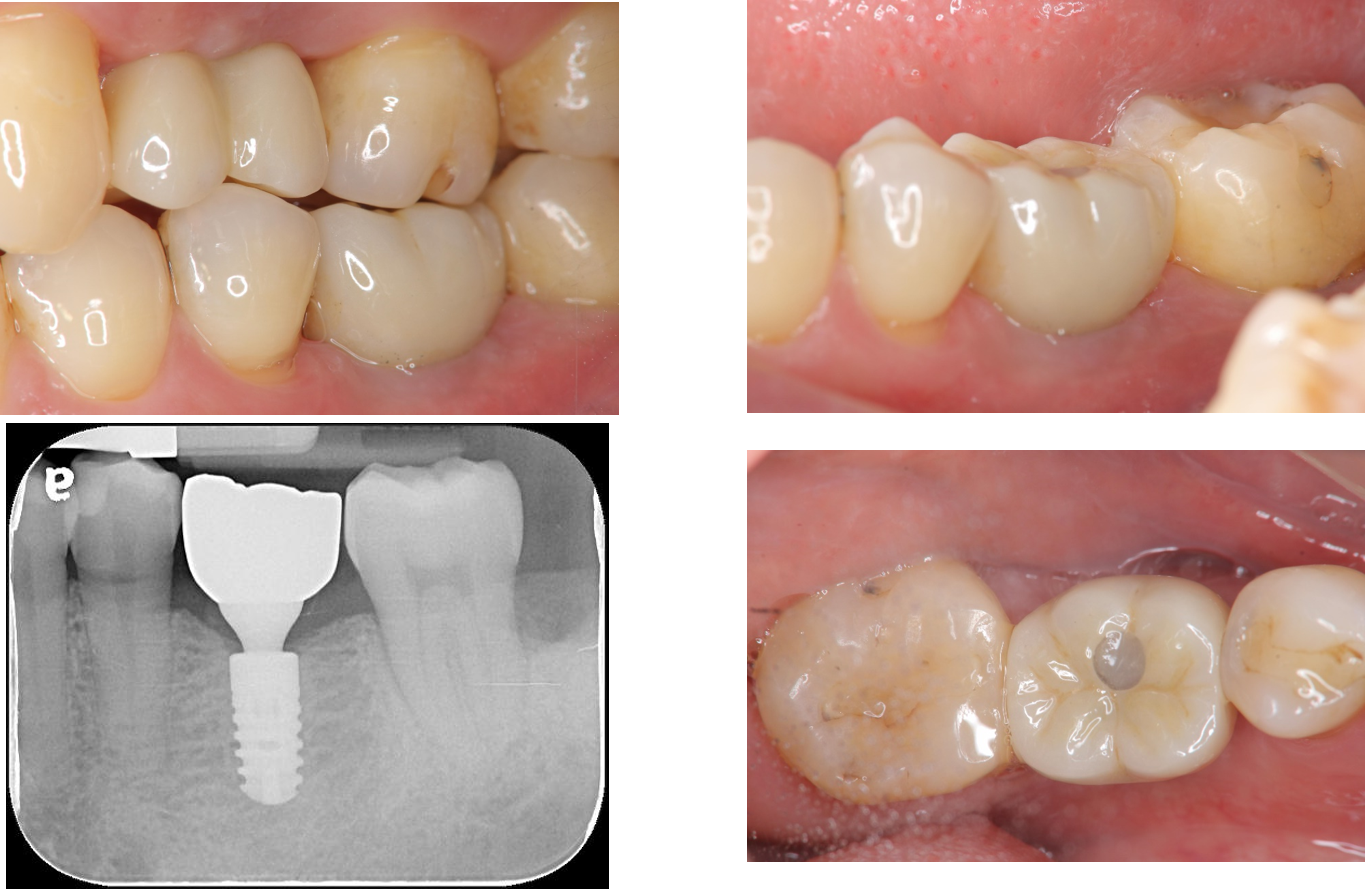

治療後,上顎植牙口內適應良好

治療後,下顎植牙口內適應良好

術前、術後比較

使用單顆植牙,不需修磨正常的牙齒,清潔更方便,且咬合更強。